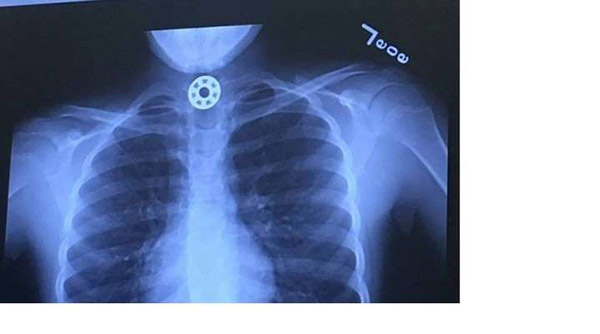

玩指尖陀螺也可以带来危险。日前,一美国女子就亲身经历过她小女儿的生死时刻,她也把这经历分享到各社交平台,让父母们都了解到这小玩具可以引起窒息的危险。她十岁的女儿,因为吞进陀螺的磁铁物体而被卡在喉咙,差点窒息死亡。这事故发生在车子内, 当时她们在回家的路上。幸好母亲及时发现状况,立刻开车到最近的医院进行急救。那里,医生们发现女孩的食道内卡有小金属物件。